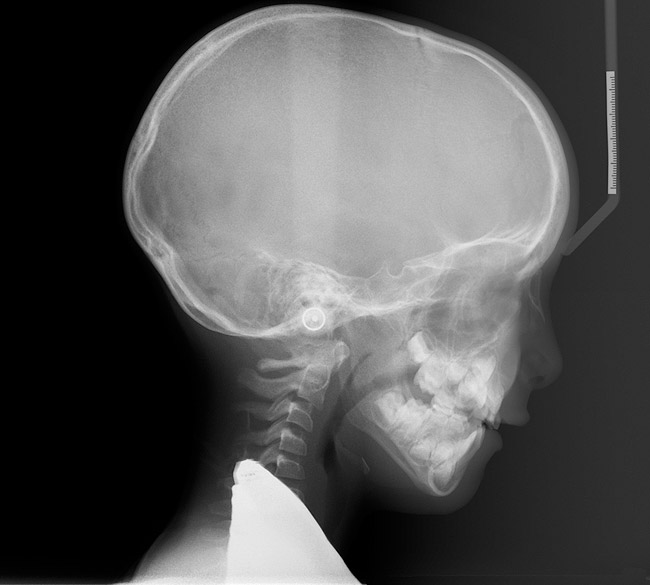

(15.) Cephalometric evaluation demonstrates significant tonsillar blockage of the airway and bimaxillary retursion.

Figure 15